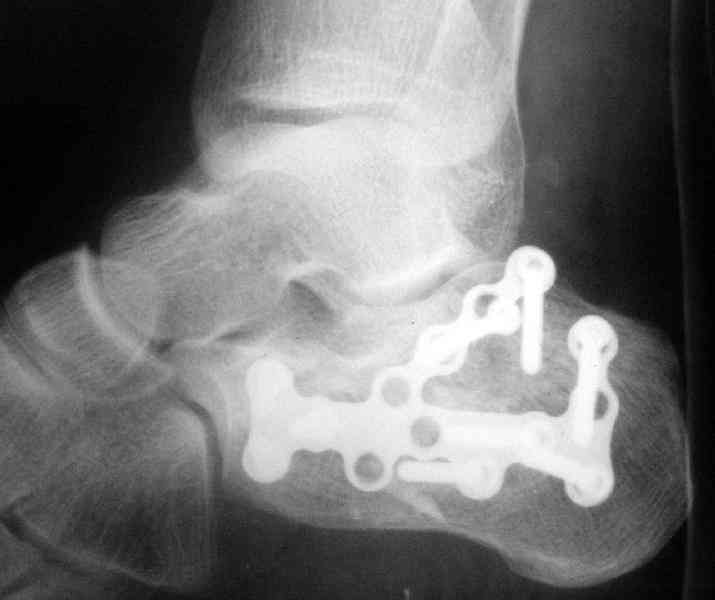

Пяточной пластиной

Открытый и закрытый способы лечения.

Its a comminuted one.

I myself would reduce it with EX-FIX and depending on the result would consider a plate on the table.

MOST OF MY COLLEGUES WOULD OPEN IT LATERALLY( a flap) and having a proper reduction would put a plate.